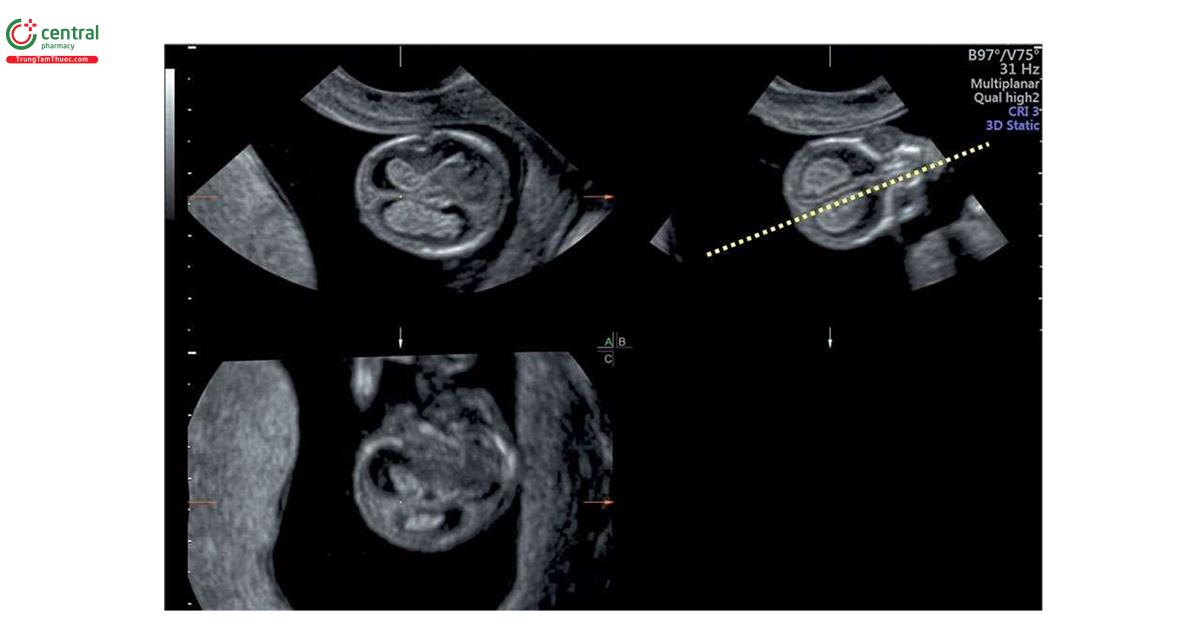

Узи первого триместра форум

Узи первого триместра форум 117 фото